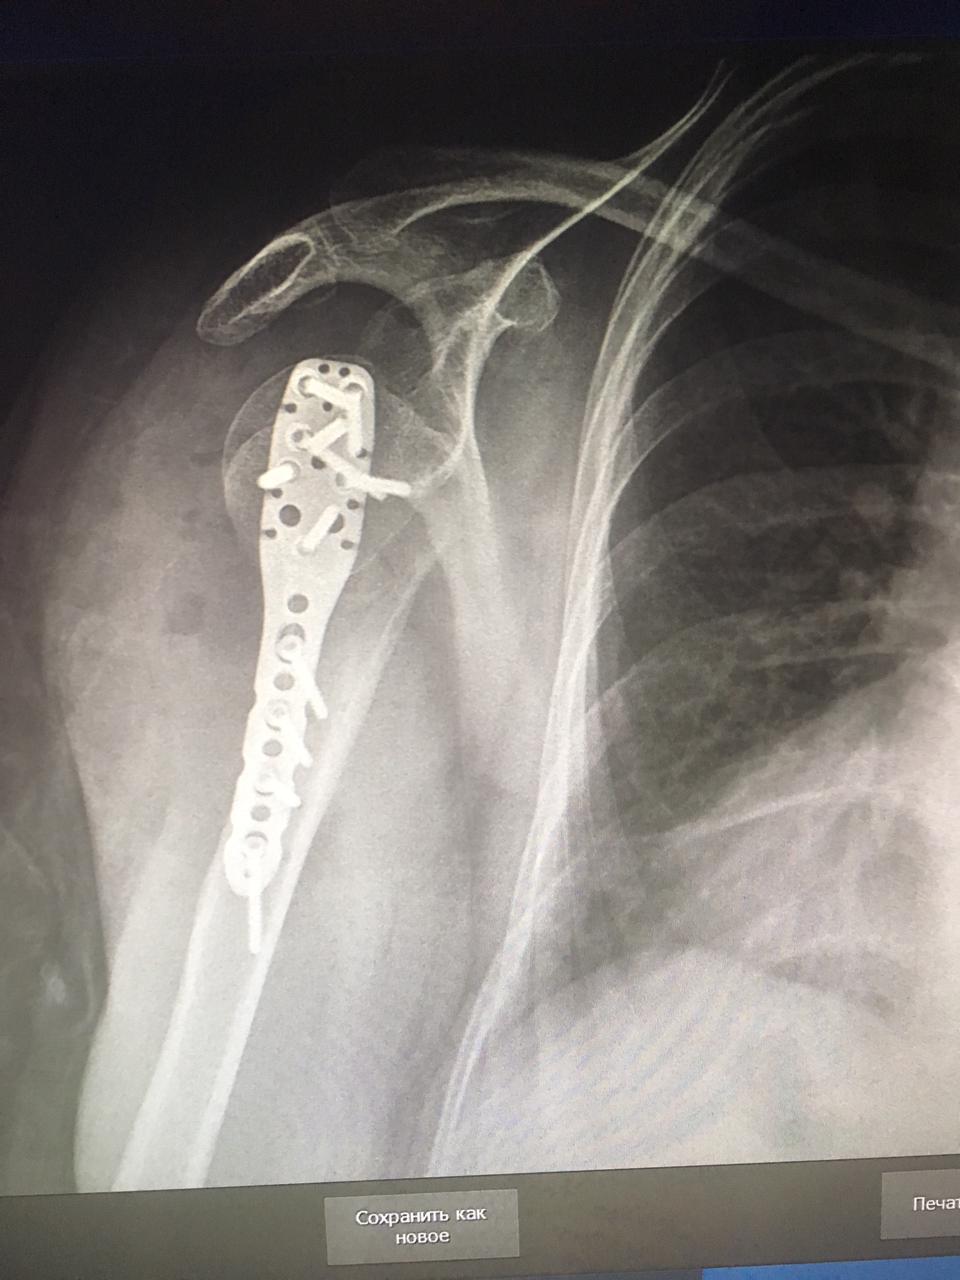

01.06.2021 жылы Жалағаш аудандық ауруханасының хирургия бөліміне жедел түрде Мәжитова Салима 1965ж.т. науқас келіп түсті. Науқастың түскен кездегі диагнозы "Сол жақ иық сүйегі мойнының жабық сынығы, ығысумен, үлкен төмпешіктің жұлынуымен". Науқасқа жедел түрде облыстық медициналық орталықтың травматолог дәрігері Рахманұлы Нұрманның қатысуымен, хирургия бөлім меңгерушісі Мұрат Оспанов және хирургия бөлімшесінің травматолог дәрігері Жарқынбек Сыдықов ота жасады. Ота барысы электронды рентген аппараты бақылауымен жабық орнына келтіру, спица арқылы бекіту тәсілімен жасалды. Аталған ота қазіргі кезде дейін тек қана облыс көлемінде жасалып келген. Аудан дәрігерлерінің біліктіліктерін уақытылы арттыру нәтижесінде күрделі оталар енді аудан көлемінде жасалады. Ауруханамыздың дәрігерлеріне алдағы уақытта жұмыстарына тек сәттілік тілейміз! Науқастардан тек қана алғыс алуларына тілектеспіз!